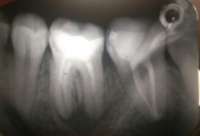

Как и обещал. Забавно, в зеркале кажется не так криво.

Боль на третий день похожа на второй день, спасаюсь болеутоляющим. Но целом уже привык.

Вчера делал панорамный снимок. Всё как >>513480 сказал, ортодонт взял его только посмотреть. Внимание, вопрос знатокам, ортодонт посмотрел на второй пикрелейтед и сказал, что зуб в котором штифт нужно переделывать - канал не полностью залечили, а так же второй зуб - там тоже проблема с каналом и что если ставить брекеты, то им обоим придет пизда. Когда это лечить не понятно, времени в обрез, завтра пойду к своему врачу который год-полтора назад мне эти зубы лечил, послушаю что скажет. В то, что она плохо сделала не хочется верить, но нужно быть реалистом.

>>514182

Да, надо перелечивать тот что левый (без штифта). Там Уже процесс в области верхушки корня есть как мне кажется, а то что я прав 99.9999% , а тот что со штифтом надо вообще посмотреть на прицельном снимке. Мне он не очень нравится.